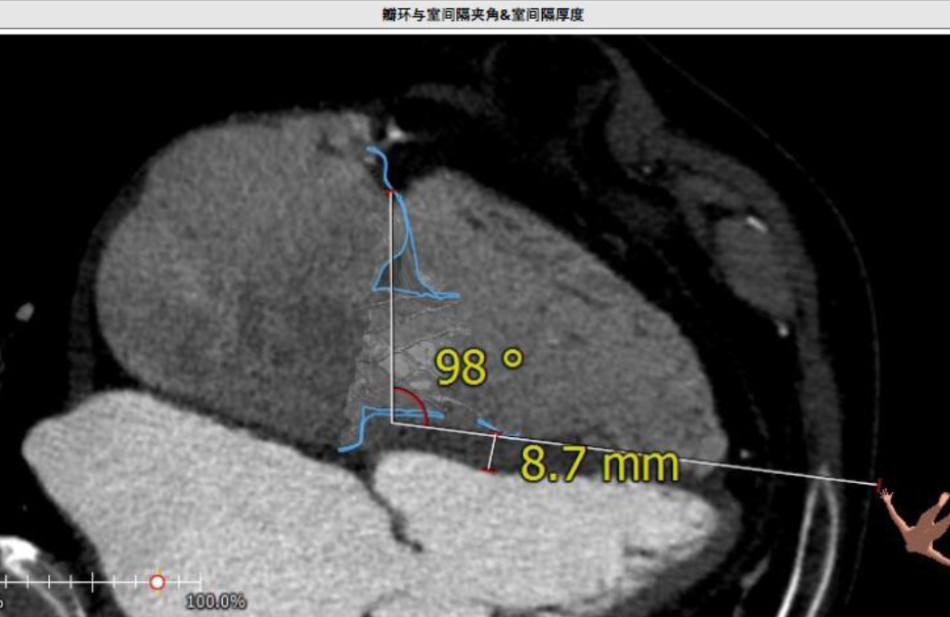

术前CT评估资料

根据术前CT的测量结果,选择使用JS/TTVI28-55号的LuX-Valve®瓣膜。